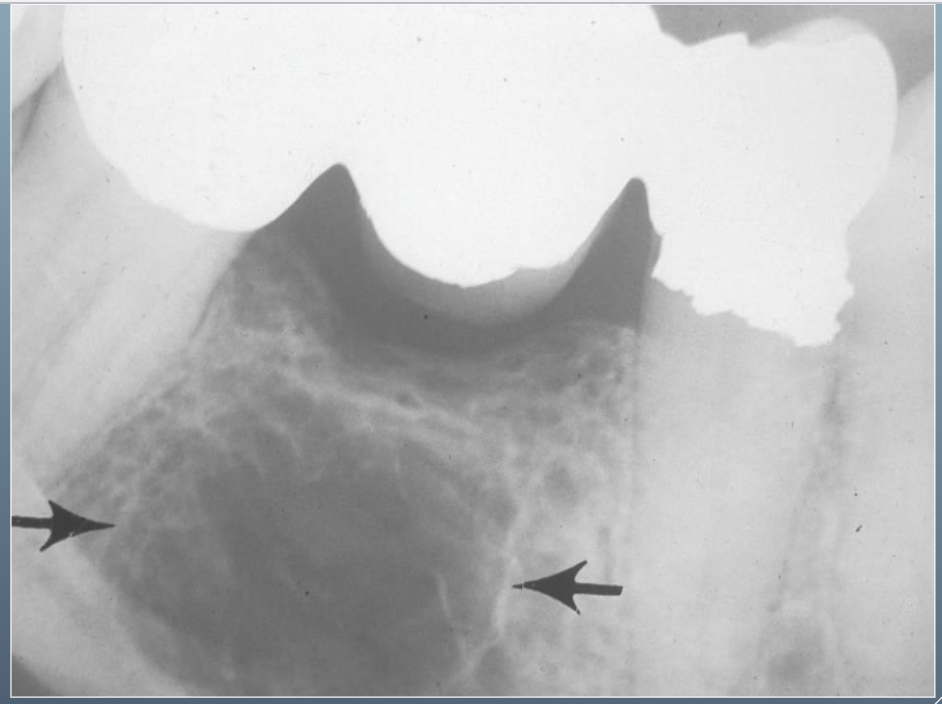

9

What’s this?

HEMATOPOIETIC BONE MARROW DEFECT

FOCAL OSTEOPOROTIC BONE MARROW DEFECT